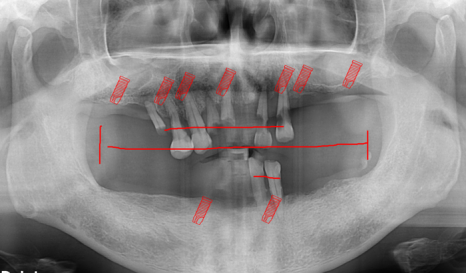

파노라마 사진과 3D 사진으로

정확하게 진단을 했습니다.

촬영:2023년 9월 25일

예상했던 것처럼

뿌리만 남아있는 치아가 많고

부러져있는 치아도 있었지만

아래는 치조골의 양이 충분했지만

상악은 어금니 부위의 치조골이 부족한 상태였습니다.

치아 중에서는 사용할 수 있는 치아가 없어서

전악 발치하는 것으로 최종적으로 진단을 내렸습니다.

환자분은 단순틀니는 원치 않으셨고

위/아래 모두 임플란트 틀니를 원하셨습니다.

위에는 4개 / 아래 2개를 원하셨는데

저희 송파 치과에서는 위에 4개의 경우

오버덴처의 장기 결과가 좋지 않아서 추천드리지 않습니다.

그래서 위의 경우에는 7개의 임플란트를 이용한 전체 임플란트 혹은 풀아치

아래는 2개를 이용한 임플란트 틀니를 이용한 방법으로 계획을 세워드렸습니다.

이렇게 치과를 내원하지않고

방치한 환자분들의 경우에는

진단 및 계획에 있어서 '잇몸뼈'의 유무가 중요한 부분인데

저희 송파 치과에서는 상악의 경우 저희 의료진이

다양한 방법으로 어떻게든 잇몸뼈를 만들어

임플란트를 식립해 드리고 있습니다.

다만, 하악의 경우 하치조 신경관으로 인해

잇몸뼈 이식과 임플란트를 할 수 있는

적정선이 있기 때문에 부작용이 발생하지 않는 선에서

환자분께 적용할 수 있는 치료 계획을 세워

진료해야 하는 상태입니다.

* 진료계획 *

상악 - 임플란트 식립 및 상악동 거상술

하악 - 임플란트 틀니